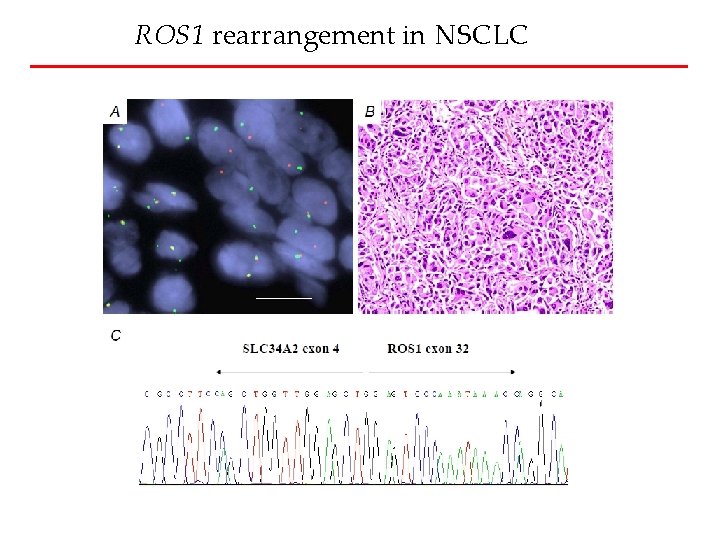

ROS 1 rearrangement in NSCLC

ROS 1 rearrangement in NSCLC